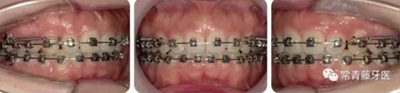

治療12個月,更換為0.018*0.025”不銹鋼方絲,鎳鈦螺旋彈簧牽引內(nèi)收上牙列,同時下頜配合Ⅱ類牽引。

治療15-22個月,弓絲打搖椅,進(jìn)一步控根內(nèi)收。

治療23個月結(jié)束。可見兩側(cè)尖磨牙達(dá)到中性關(guān)系,上下牙列排齊整平,前牙覆合覆蓋正常,中線齊。